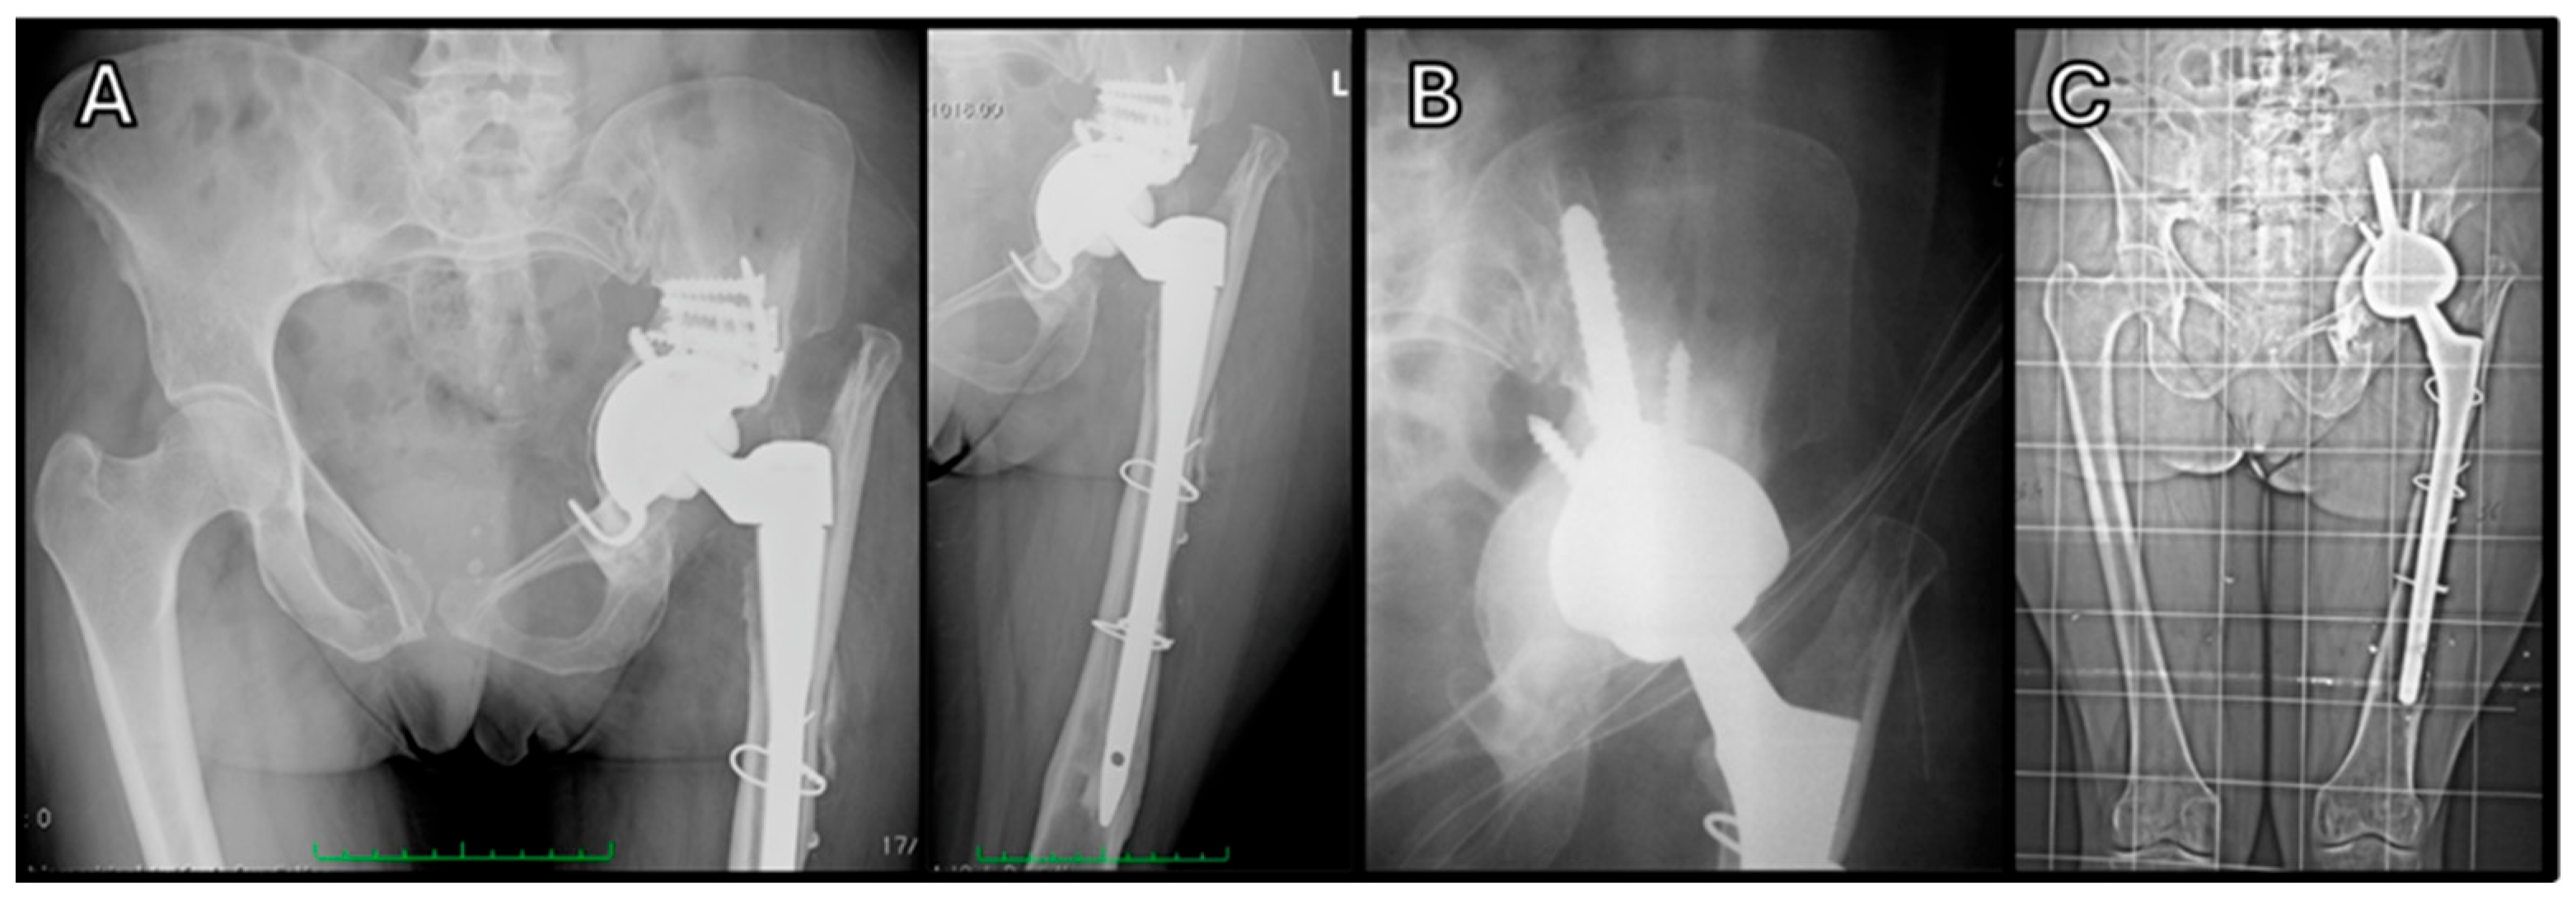

- Cadossi, M.; Garcia, F.L.; Sambri, A.; Andreoli, I.; Dallari, D.; Pignatti, G. A 2- to 7-Year Follow-Up of a Modular Iliac Screw Cup in Major Acetabular Defects: Clinical, Radiographic and Survivorship Analysis With Comparison to the Literature. J. Arthroplast. 2017, 32, 207–213. [Google Scholar] [CrossRef]

| M. Cadossi et al. 2017 [64] | Major acetabular defects | 121 hips | Sansone Cup (Cittiefe) | 46 Months | Postoperative complications: 4.2% infections; 2.5% dislocations; 0.8% loosening; 4.2% implant removed. |